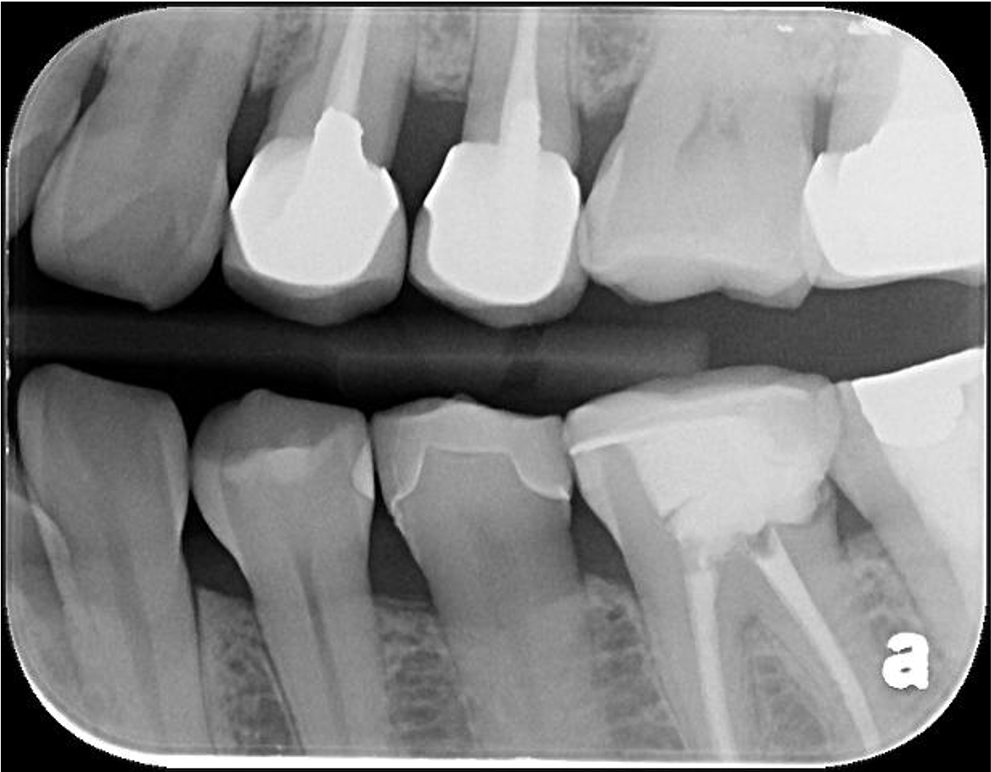

X光顯示密合度良好無殘膠